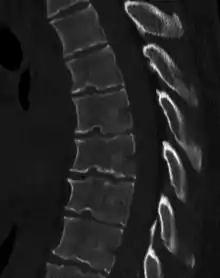

Scheuermann's disease

Scheuermann's disease is a self-limiting skeletal disorder of childhood. Scheuermann's disease describes a condition where the vertebrae grow unevenly with respect to the sagittal plane; that is, the posterior angle is often greater than the anterior. This uneven growth results in the signature "wedging" shape of the vertebrae, causing kyphosis. It is named after Danish surgeon Holger Scheuermann.[3][4][5]

Diagnosis is typically by medical imaging. The degree of kyphosis can be measured by Cobb's angle and sagittal balance.